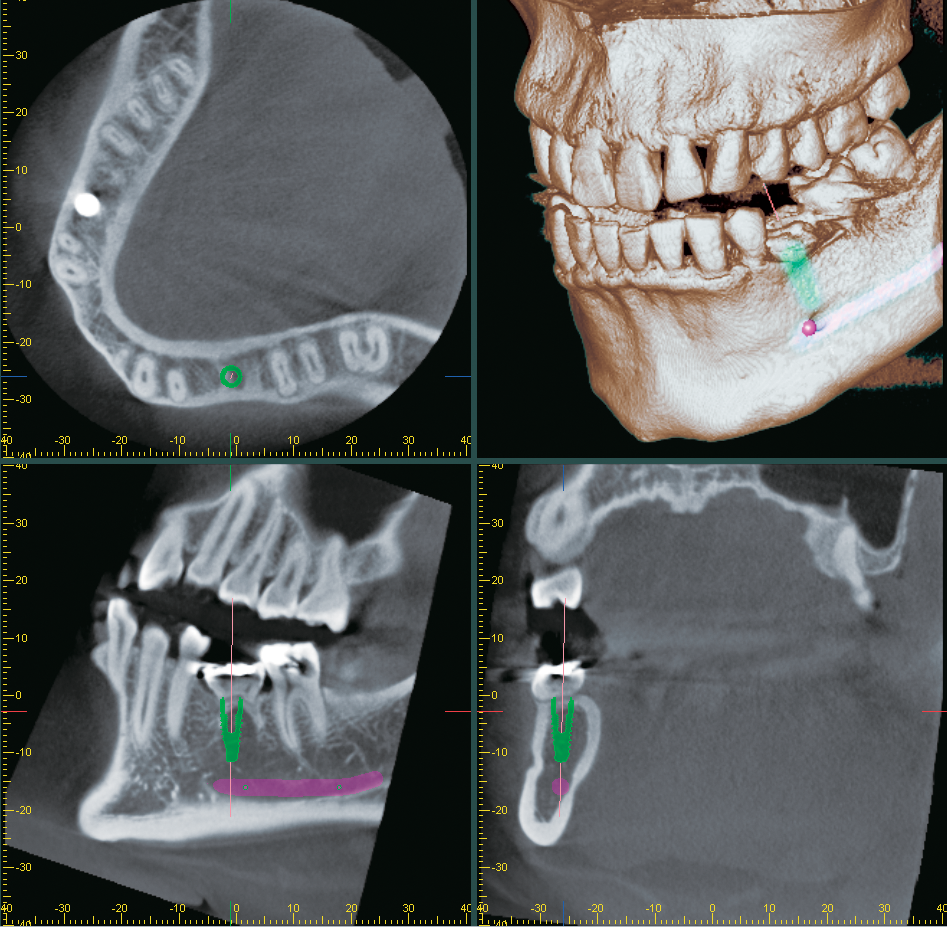

Morita i-Dixel imaging software presents a wide variety of services to its users ensuring they reach an accurate diagnosis for their cases. The software features a drawing function, presentations for implant therapy, and the ability to convert 3-dimensional x-rays to solid images to allow for rotation, magnification, and slicing of the image. i-Dixel also has the ability to view both CT slice images and volume-rendered images simultaneously on the computer screen.